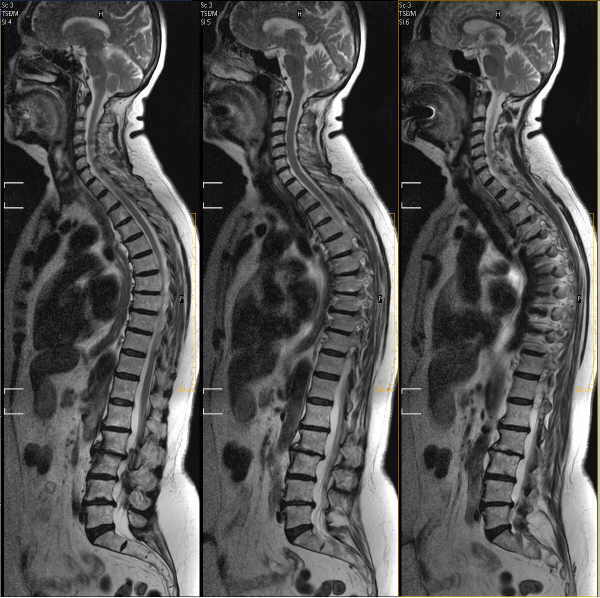

La resonancia magnética nuclear (RMN) es un examen médico no invasivo que ayuda a que los médicos diagnostiquen y traten enfermedades.

La RMN emplea un campo magnético potente, pulsadas de radiofrecuencia y una computadora para crear imágenes detalladas de los órganos, tejidos blandos, huesos, y prácticamente el resto de las estructuras internas del cuerpo. De esta forma, las imágenes pueden examinarse en el monitor de una computador, transmitirse electrónicamente imprimirse o copiarse a un CD. La RMN no utiliza radiaciones ionizantes (rayos X).

Por lo general, la diferenciación entre tejido anormal (enfermo) y tejido normal es a menudo mejor con la RMN que con otras modalidades de imágenes tales como rayos-X, TAC y ultrasonido.

Debido a que la RMN puede dar imágenes tan claras de los tejidos blandos alrededor de los huesos, es el examen más sensible para los problemas de la columna y las articulaciones.